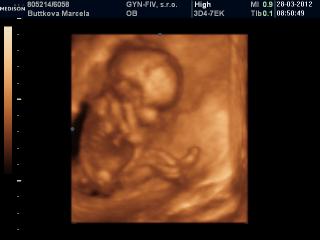

@tominka...ja som bola na 3D/4D pri malom v 23tt...pozri na foto co mam v albume, podla mna velmi pekne.

@tomika kvalita závisí od prístroja ktorý doki používa. Ja som bola na 3/4D v 16tt (viď foto) a idem ešte v 26tt. Ale čím skôr ideš tým viac sa bábo podobá na mimozemšťana 😀 😀 😀 možno preto ti vravela, že je lepšie ísť v 24-28tt. Keď je to ešte neskôr, bábätko už má málo miestečka a to tiež nie je veľmi dobre vidno vtedy. Ale zasa ak vám to vychádza najlepšie na budúci týždeň, myslím, že lepšie skôr ako nikdy 🙂

@marcelatje dakujem,a krástne vidno aj v 16tt,kvelitné fotky.No,nás objednal na 4.5.Dufam že volačo uvidime 🙂 .Predchádzajucich tehu sme neboli na 3D.Tak teraz pojdeme.Ibaže mm teraz robi v zahraniči,a nevieme kedy nabuduce pride domov..Teraz je doma,tak teraz pojdeme 😉 .